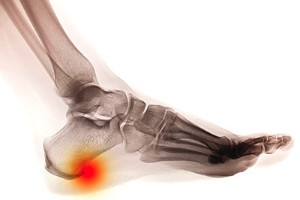

A condition referred to as a heel spur is typically caused by repetitive stress placed on the foot. Gradually, a small protrusion forms on the bottom of the heel, and often produces severe pain. As a result, walking may become difficult, which may affect the gait. Research has shown that it is suggested to stop the activity that has caused the heel spur to develop, followed by implementing proper treatment methods. These may consist of injections that to provide relief, in addition to performing stretching techniques that may help in maintaining an accepted level of comfort. Surgery may be an additional option for permanently removing the heel spur and improving the general mobility of the entire foot. Most patients experience heel pain which typically precedes a proper diagnosis, and should not be ignored. Please consider scheduling a consultation with a podiatrist for additional information on how to properly treat heel spurs.

Heel spurs can be incredibly painful and sometimes may make you unable to participate in physical activities. To get medical care for your heel spurs, contact one of our podiatrists from Pennsylvania Foot & Ankle. Our doctors will do everything possible to treat your condition.

Heels Spurs

Heel spurs are formed by calcium deposits on the back of the foot where the heel is. This can also be caused by small fragments of bone breaking off one section of the foot, attaching onto the back of the foot. Heel spurs can also be bone growth on the back of the foot and may grow in the direction of the arch of the foot.

Older individuals usually suffer from heel spurs and pain sometimes intensifies with age. One of the main condition's spurs are related to is plantar fasciitis.

The pain associated with spurs is often because of weight placed on the feet. When someone is walking, their entire weight is concentrated on the feet. Bone spurs then have the tendency to affect other bones and tissues around the foot. As the pain continues, the feet will become tender and sensitive over time.

Heel spurs are the result of calcium deposits that cause bony protrusions on the underside of the heel. Heel spurs are usually painless, but they have the potential to cause heel pain. Heel spurs tend to be associated with plantar fasciitis, which is a condition that causes inflammation of the band of connective tissue that runs along the bottom of the foot. They most often occur to athletes whose sports involve a lot of running and jumping.

Some risk factors for developing heel spurs include running and jogging on hard surfaces, being obese, wearing poorly fitting shoes, or having walking gait abnormalities.

It is possible to have a heel spur without showing signs of any symptoms. However, if inflammation develops at the point of the spur’s formation, you may have pain while walking or running. In terms of diagnosis, sometimes all a doctor needs to know is that the patient is experiencing a sharp pain localized to the heel to diagnose a heel spur. Other times, an x-ray may be needed to confirm the presence of a heel spur.

Heel spurs can be prevented by wearing well-fitting shoes that have shock-absorbent soles. You should also be sure that you are choosing the right shoe for the activity you want to partake in; for example, do not wear walking shoes when you want to go on a run. Additionally, maintaining a healthy weight can be beneficial toward preventing heel spurs, as it will prevent an excess amount of pressure being placed on the ligaments.

There are a variety of treatment options for people with heel spurs. Some of these include stretching exercises, physical therapy, shoe inserts, or taping and strapping to rest stressed muscles and tendons. If you have heel pain that lasts longer than a month, don’t hesitate to seek help from a podiatrist. Your doctor can help you determine which treatment option is best for you.